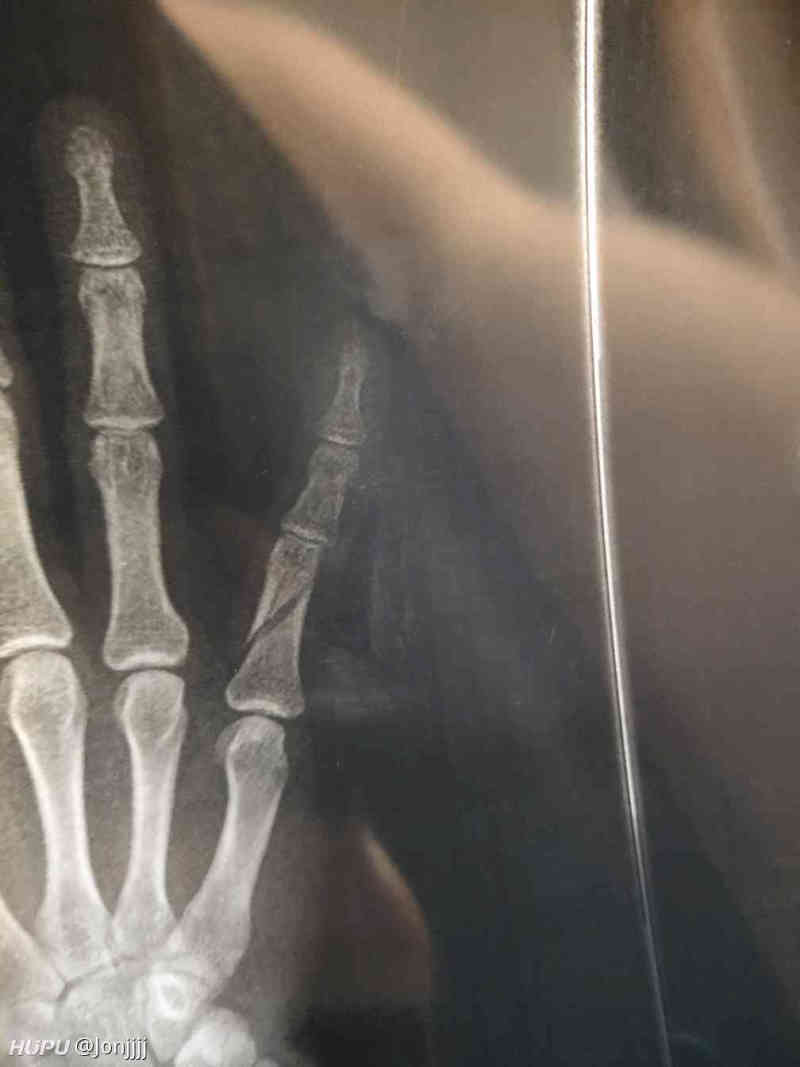

记录一下骨折的恢复过程 虎扑

今晚打球小拇指错位骨折 有懂的老哥吗 虎扑